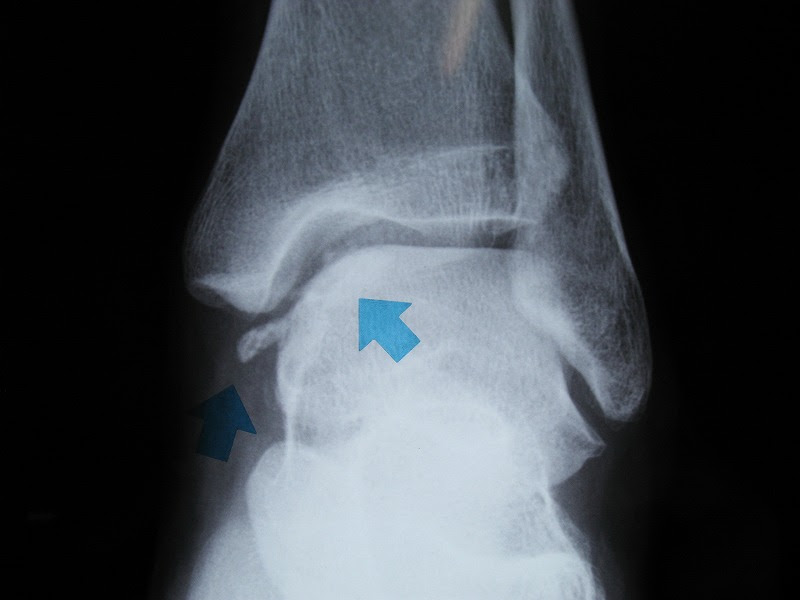

家庭医学館 関節遊離体(関節鼠)の用語解説 どんな病気か 主として軟骨や骨の小片が、関節内に遊離して動きまわるものを、関節遊離体あるいは関節鼠といいます。 このようなことがおこる原因としては、離断性骨軟骨炎(りだんせいこつなんこつえん)、骨軟骨腫症(こつなんこつしゅ 膝の関節ネズミの治療法とは? さて、ここからは膝関節に現れる通称「ネズミ」と呼ばれている関節内遊離体の治療法について紹介してまいりましょう。 関節内遊離体は、骨軟骨片が完全に剥離して関節内を移動しているものを指します。 骨軟骨片が